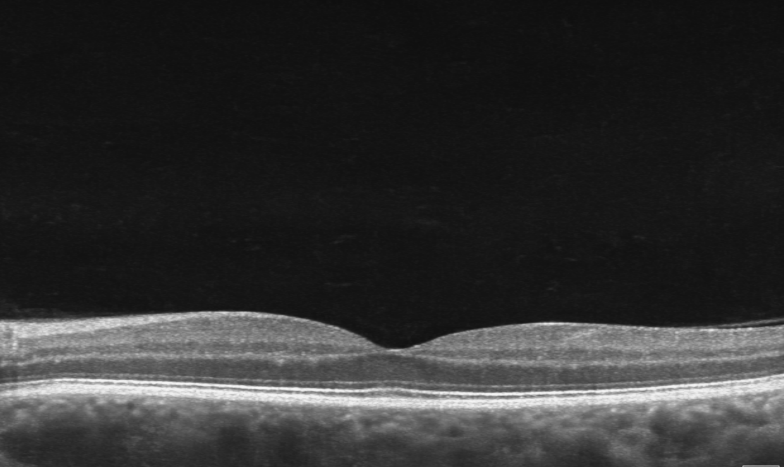

OCT image of normal macula

OCT image of drusen in Macular Degeneration